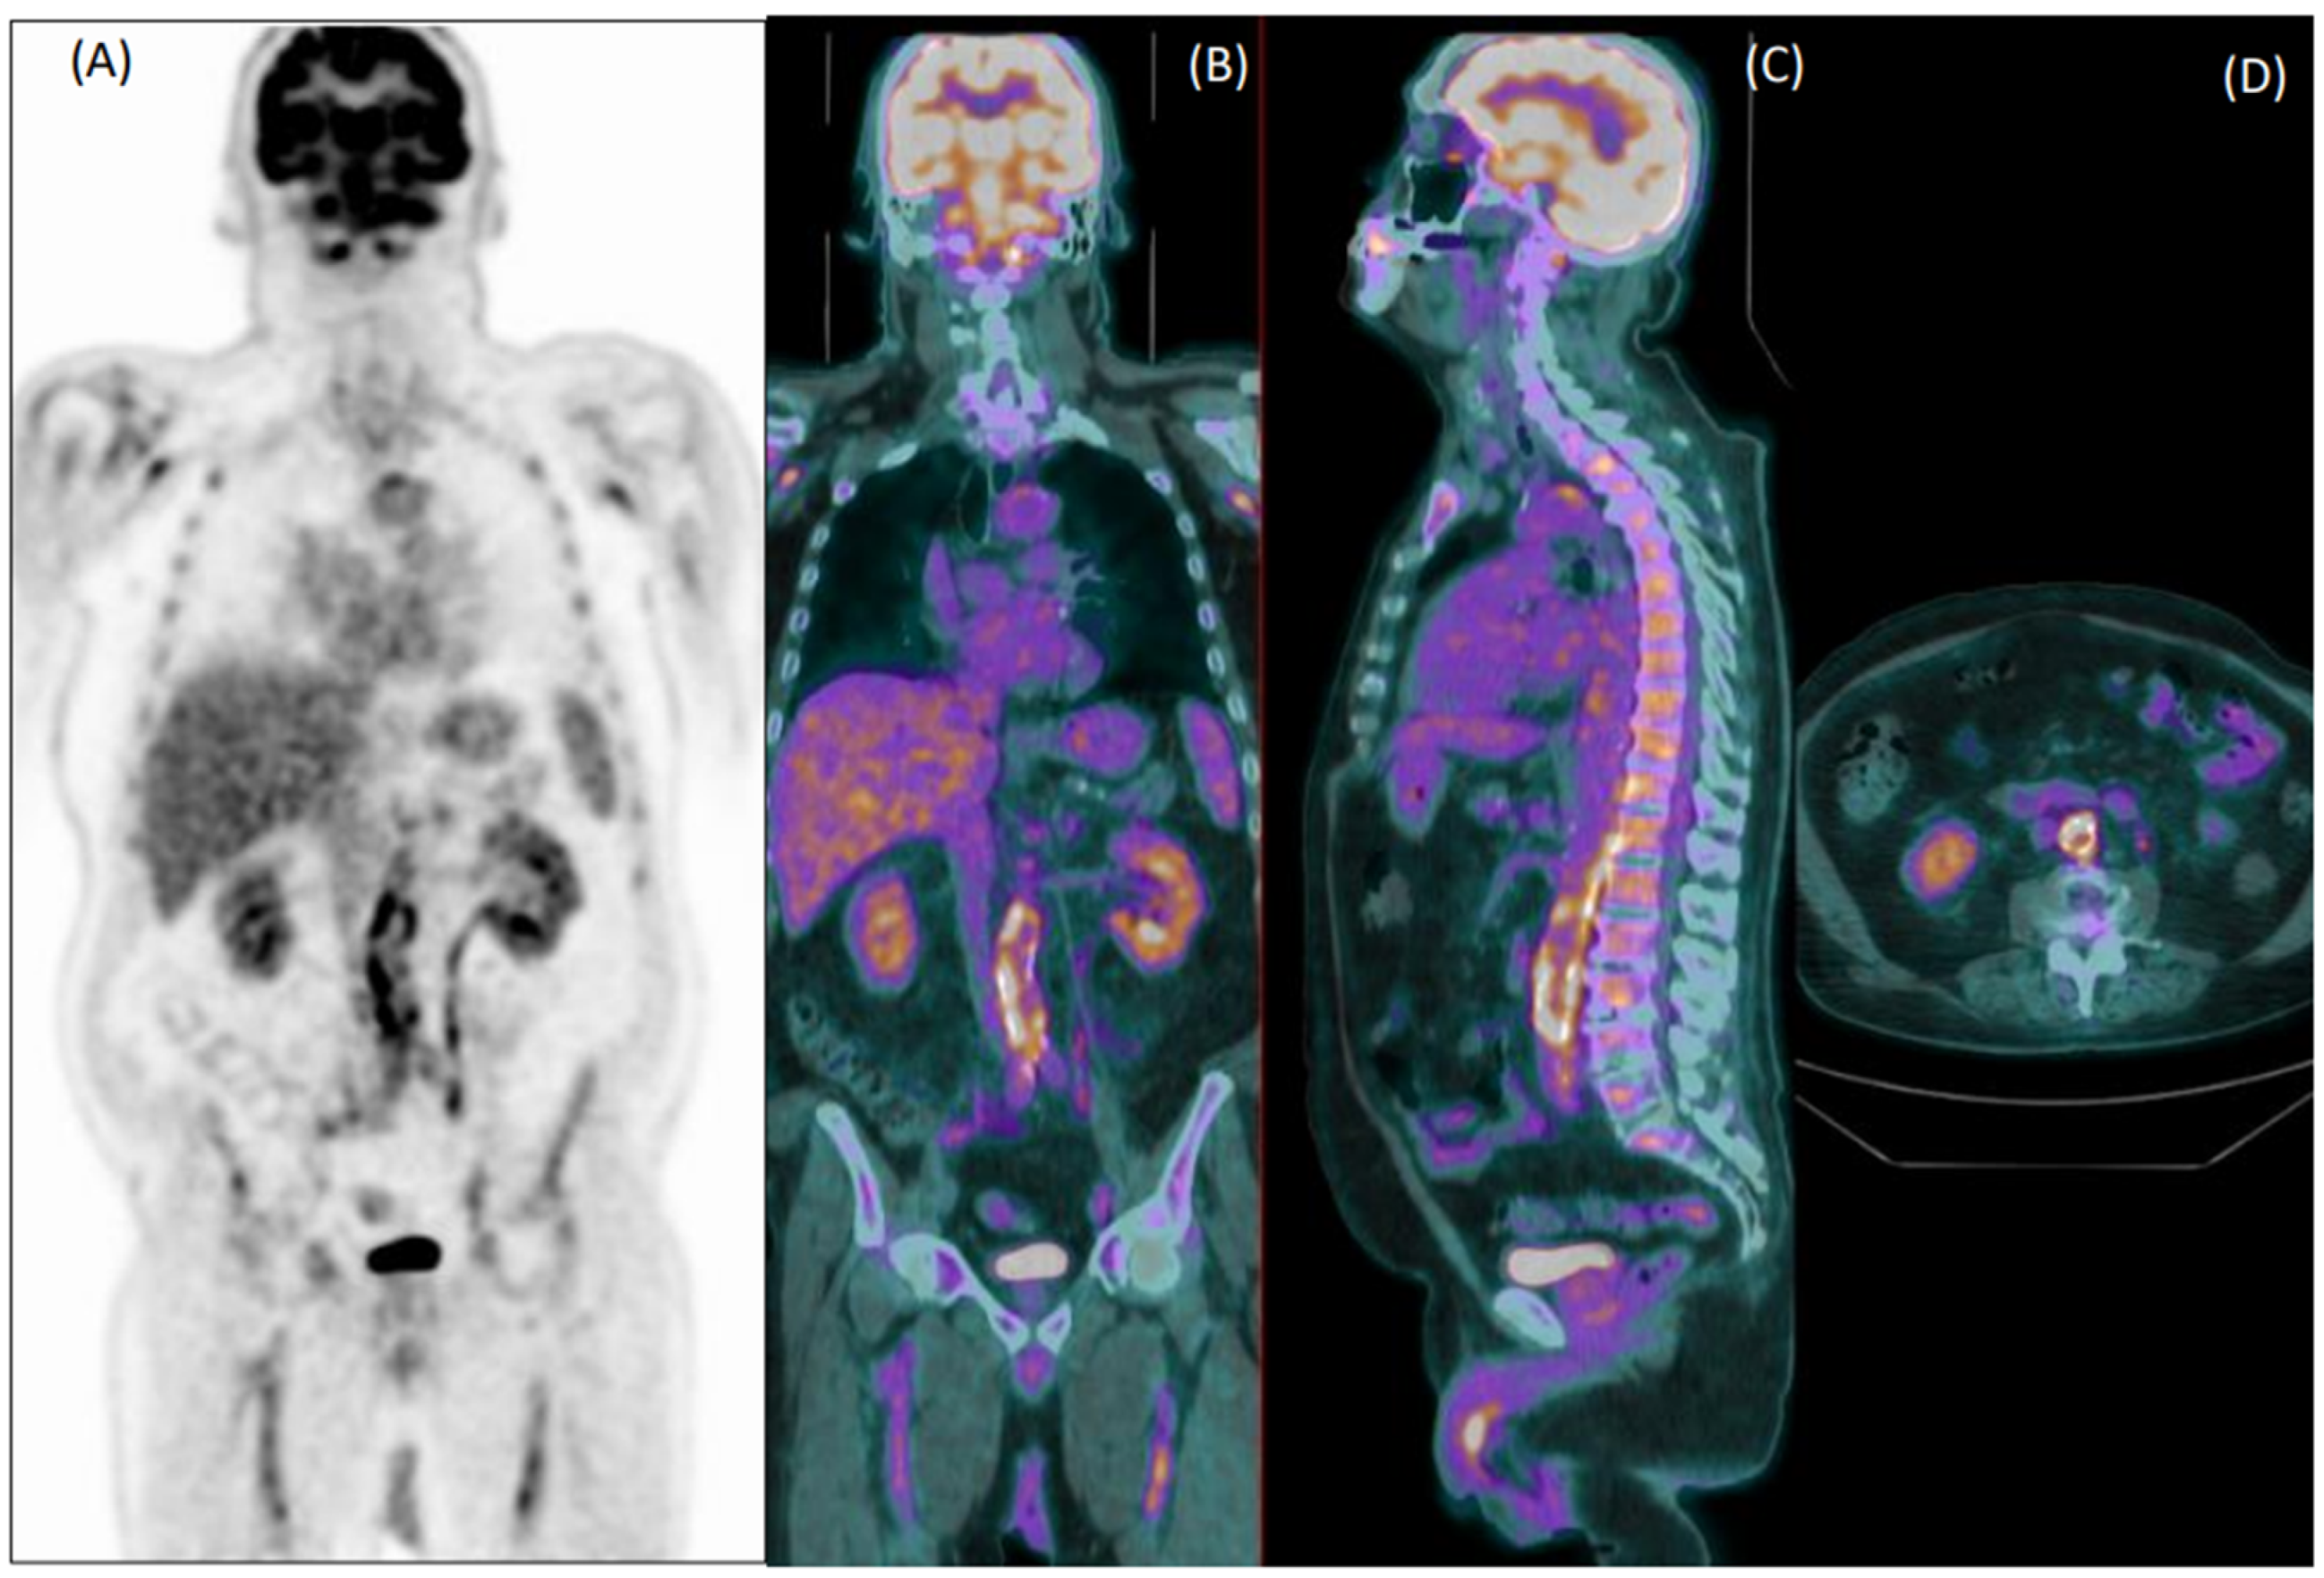

In total, 81 patients (29%) were clinically diagnosed with LVV. Reader 1 and reader 2 failed diagnosis in 76 patients (37 false negative and 39 false positive) and 92 patients, respectively (33 false negative and 59 false positive). Figure 1 and Figure 2 show examples of a true positive and a false positive PET exam. Among the 76 patients wrongly classified by reader 1, 51 were >65-years-old, 44 were overweight, 46 were taking steroids, 12 presented with hyperglycemia, 29 were early acquired, while in 26 patients, the acquisition was delayed, and 23 were scanned with P1.

Figure 1. Coronal [18F]FDG PET (A) and fused PET/CT coronal (B), sagittal (C) and axial (D) images of an 80-year-old male patient with fever of unknown origin. Images show diffuse increased uptake in the abdominal aorta, common iliac, and femoral arteries. Both readers evaluated this exam as positive for vasculitis, which was confirmed during clinical follow-up.